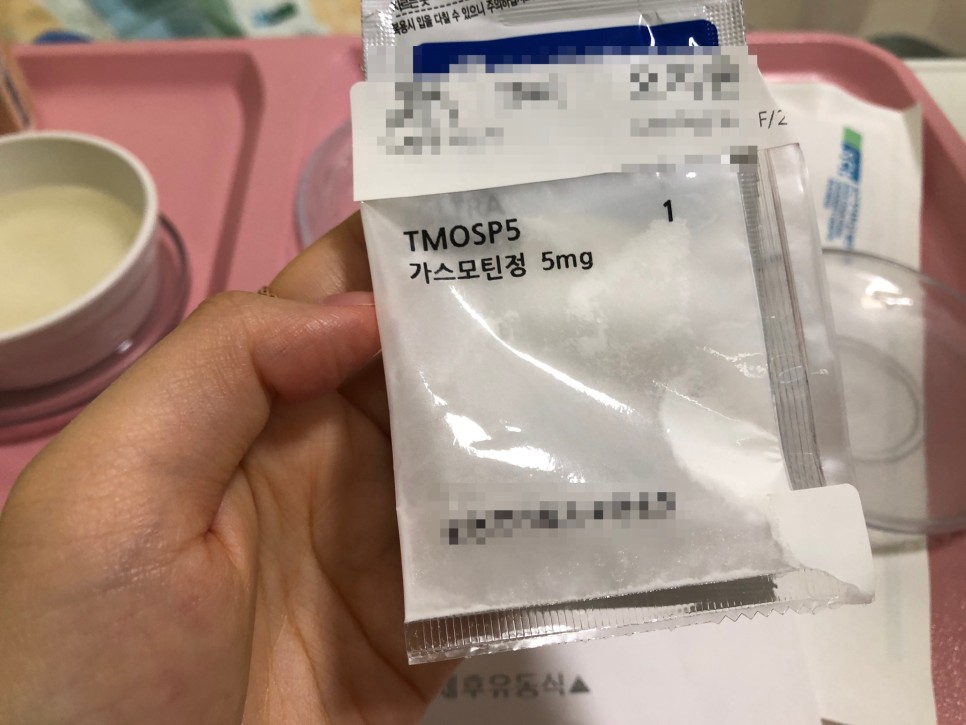

이건 수술하면 주는 우의약이지만 하루에 2~3회씩 양치질을 하고 토하면 돼요

약 다 먹으면 가루약+시럽약 먹어요!